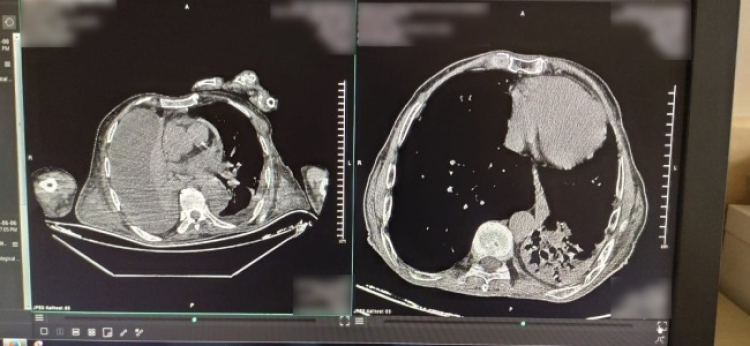

Bursa Yüksek İhtisas Eğitim ve Araştırma Hastanesi'nde yanlış teşhis sonucu sonrası ciğerine müdahale yapılan hasta hayatını kaybetti. Yanlış müdahalenin hasta filmlerinin karışmasıyla gerçekleştiği ortaya çıktı. İşte detaylar...

İddiaya göre devlet hastanesinde çekilen Bilgisayarlı Tomografi'yi (BT) inceleyen alt taşeron firmasının anlaşmalı doktoru, hastanın filmine bakarak akciğerlerde sıvı birikmesi olduğunu söyledi.

"Hastanın şikayetleri artınca da, kamuda görevli hekim acil olarak işlem başlatıyor... Akciğerlerde biriktiği belirtilen sıvıyı doktor iğne ile çekiyor... Ancak, operasyondan sonra hasta ağırlaşıyor ve hayatını kaybediyor... Çünkü hastanın akciğerlerinde sıvı olmadığı için iğne batınca ciğer sönmüş... Acı olayın ardından hekim durumu araştırdığında hasta filimlerinin karıştığını tespit ediyor...Ayrıca, bir ilçe devlet hastanesinde hastanın çekilmiş olan ayrı BT’sinde akciğerlerde sıvı olmadığı da görüyor..."